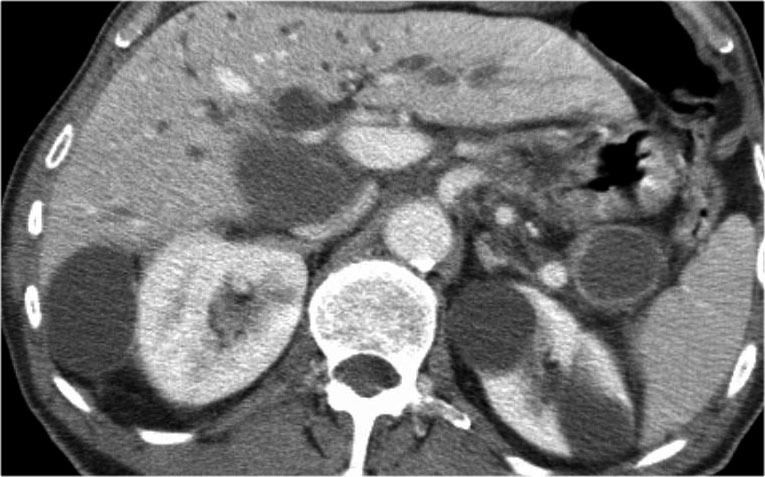

Hình ảnh CT cho thấy một nang lớn ở vùng thượng vị trên bệnh nhân có tiền sử viêm tụy cấp (Hình).

Lưu ý có thêm một ít dịch cổ trướng và dịch màng phổi.

Thành nang có ngấm thuốc.

CT cho thấy hai nang lớn ở bệnh nhân nữ 45 tuổi có tiền sử chấn thương (hình).

Lưu ý hình ảnh thâm nhiễm mỡ trong khoang sau phúc mạc (mũi tên).

Kết hợp đặc điểm hình ảnh với tiền sử lâm sàng, rất có khả năng đây là các nang giả tụy do chấn thương.